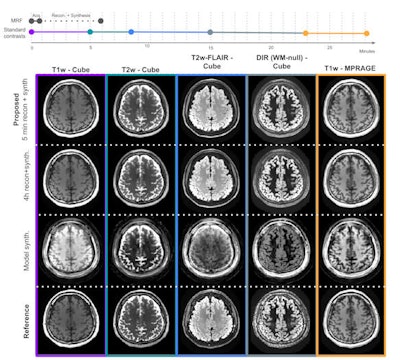

With help from a machine-learning algorithm for image synthesis, the method can provide five high-quality images with common clinical contrasts at 1-mm isotropic resolution, as well as quantitative T1, T2, and proton density maps, according to presenter Sophie Schauman and colleagues.

Compared to images reconstructed using the traditional technique that takes four hours, the fast reconstruction method has more undersampling artifacts, more blurring, and more noise, Schauman said.

"However, if this information can be recovered in the synthesis network, all of this doesn't matter at all," she said.

In the two test subjects, the synthesized T1-weighted magnetization-prepared rapid acquisition gradient-echo (MP-RAGE), T2-weighted, T2 fluid-attenuated inversion recovery (FLAIR), and double inversion recovery (DIR) images had highly similar slicewise structural similarity indexes compared with synthesized images produced from the reference reconstruction technique.